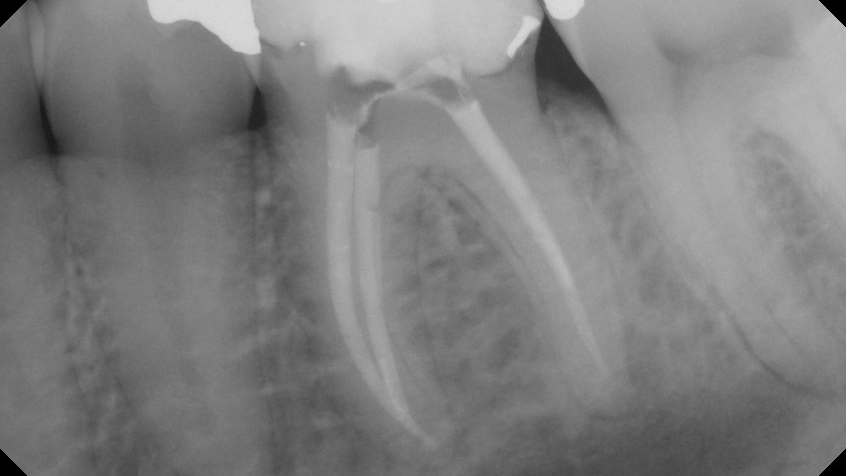

Management of second mesio-buccal canal in maxillary molars with one instrument used in reciprocation, without initial scouting and without glide path

The management of MB2 canals in maxillary molars can be challenging1 considering the complexity of the canal anatomy and the presence of calcifications.2,3 The first step in the management of a calcified MB2 canal is the initial scouting with small stainless-steel (SS) hand instruments sizes 6 to 10, which is considered as the most challenging part … Read more